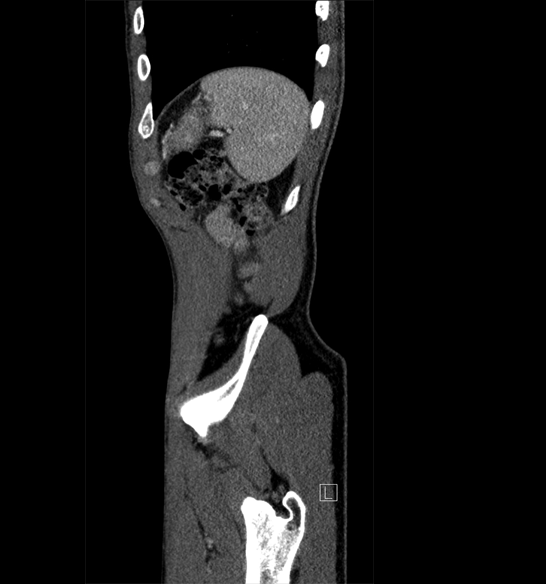

Body

Covers abdominal CT anatomy.